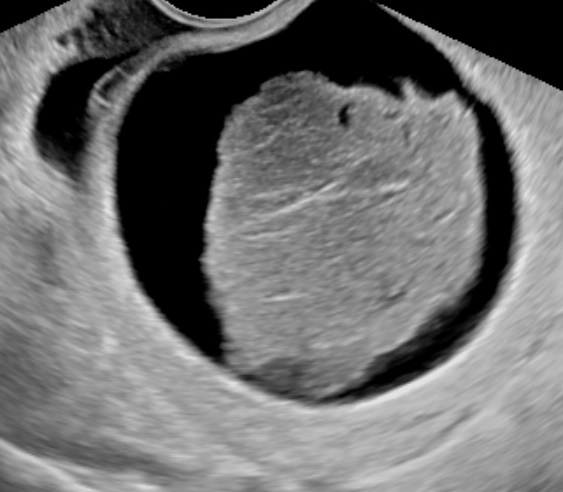

Ultrasound characteristics of adnexal torsion include:

- Presence of ovarian cyst/tumor, or parovarian cyst or hydrosalpinx (usually as a prerequisite).

- Edematous ovary and/or tube with increased intrafollicular distance and/or follicular halos.

- Abnormal or absent doppler flow inside the ovary.

- The whirlpool sign.